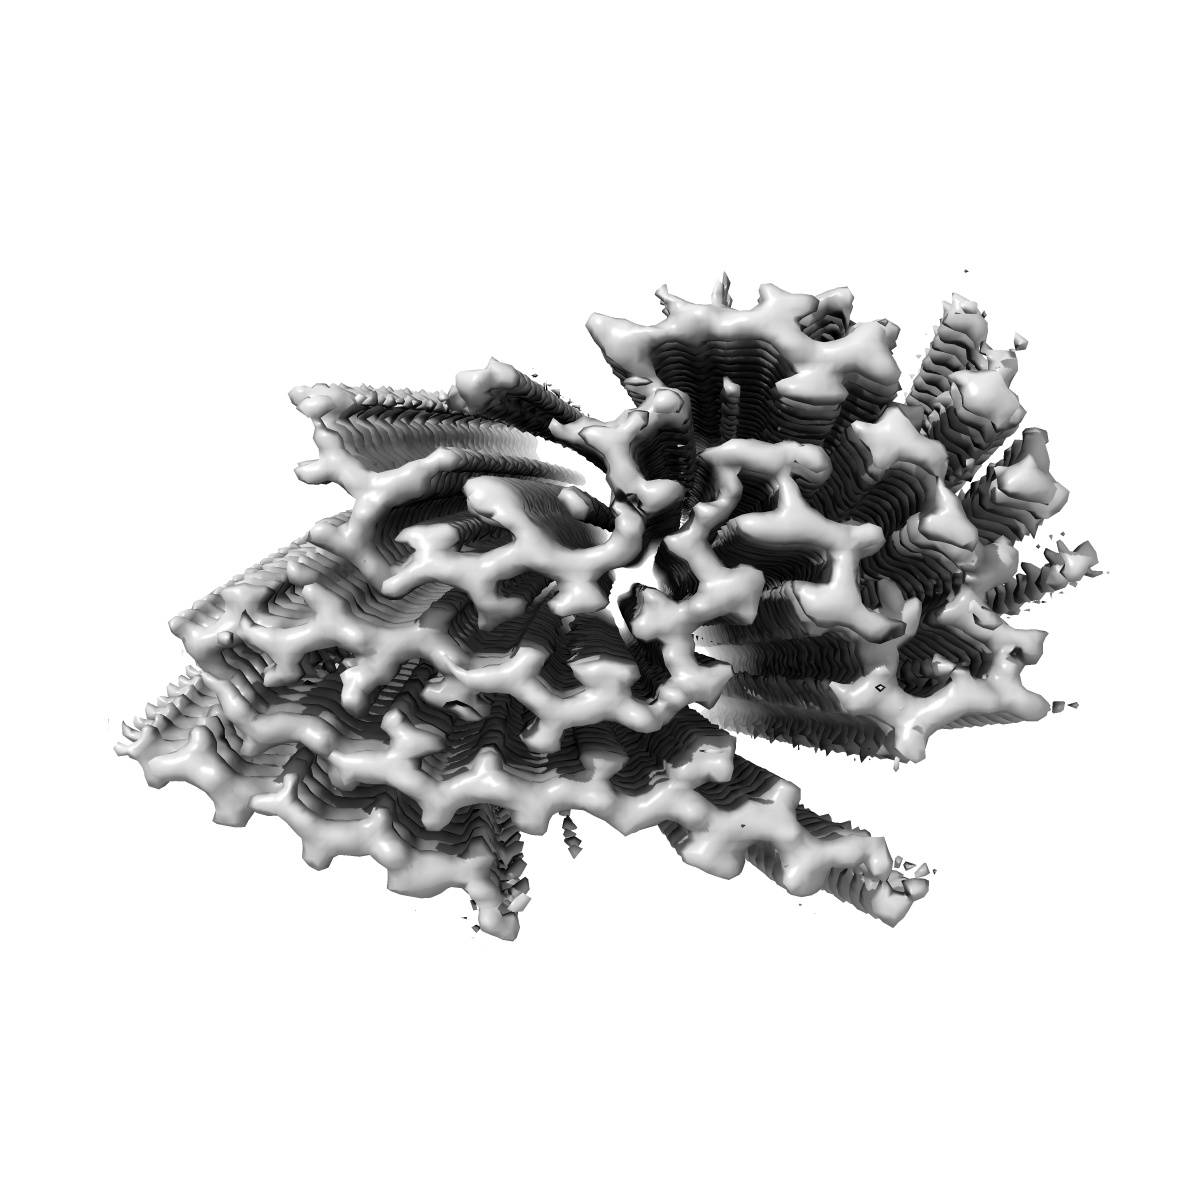

Cryo-EM structure of alpha-synuclein filaments from Parkinson's disease and dementia with Lewy bodies

Helical reconstruction2.2 Å

Sample: Alpha-synuclein filaments extracted from the human brain with PD, PDD, and DLB

Structures of alpha-synuclein filaments from human brains with Lewy pathology.

(2022) Nature , 610 , 791 - 795